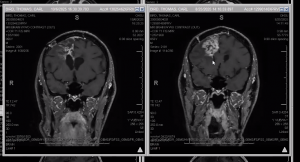

Tom had his last scan on 1/16 and the great news was it was unchanged and ruled stable. Unfortunately on Wednesday 1/28 Tom had his worst seizure yet while he was on a video call with his new counselor. He fell to the ground and was unable to respond. I was teaching Zumba and his counselor couldn’t reach me so he called 911. Tom was able to get up as the paramedics arrived and put Olive away but was still out of it and took him to the hospital. They were able to use Tom’s phone to call me which broke my do not disturb setting and I was able to leave. Our good friends and Portland family Jeff and Darrell came to meet us at the hospital. They did a CT and MRI, which they ruled unchanged so we once again do not know what brought on this seizure but it was definitely the longest most severe one Tom has had. We know it was not brought on by him being tired as he had just logged his best night of sleep ever per his Oura ring. We had a great day leading up to it and really felt like we had a handle on things so this last one, particularly the severity of it has us frustrated and depressed, not to mention that Tom has some injuries from his fall. We are very thankful he was on the call and that it was not worse, but we are still reeling. We are so grateful that so many of our wonderful friends have dropped by to see us and lift our spirits the last few days and bring food by. Our community is amazing and we are deeply grateful.